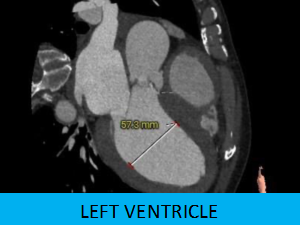

患者:老年男性,因发作性胸闷咳嗽2年,加重伴晕厥10余天收治入院,超声心动图显示主动脉瓣重度钙化增厚,回声增强,开放受限。平均跨瓣压差 48mmHg,最大压差84mmHg,瓣上速度 4.77m/s,EF32%,提示主动脉瓣重度狭窄并伴有轻度关闭不全。

1.主动脉瓣瓣环周长90.9mm,平均周长径28.9mm。